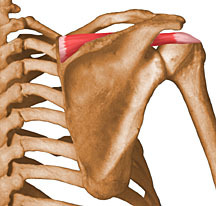

DIGA O NOME DESTE MÚSCULO

MÚSCULO SUPRAESPINHOSO